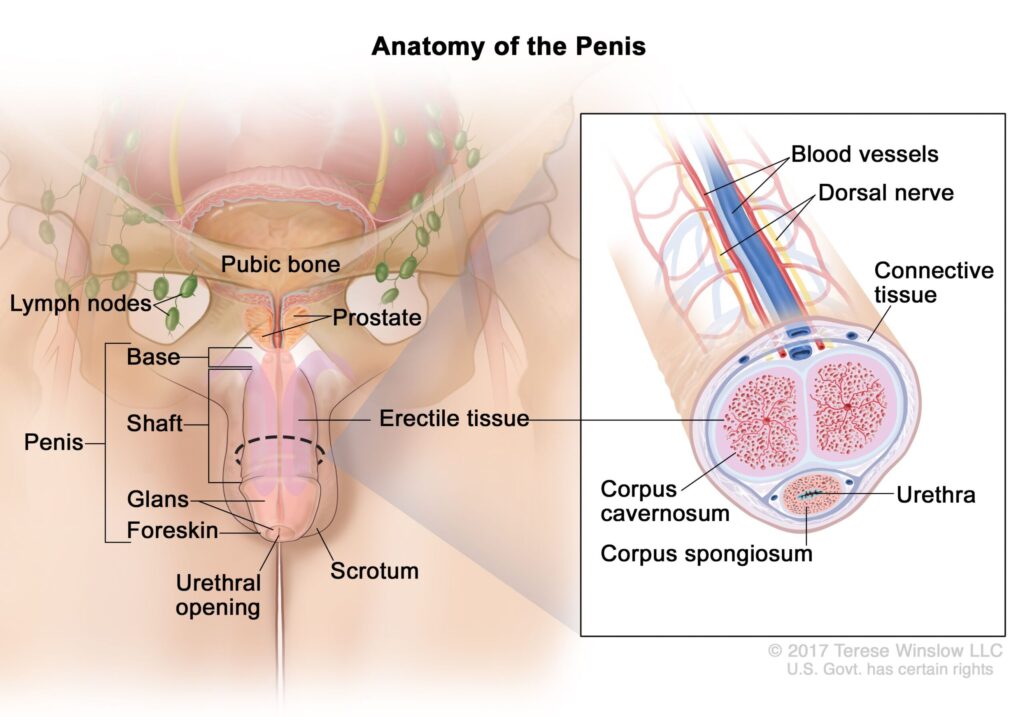

Your sexual performance isn’t just about what happens “down there.”

It’s controlled by a delicate network of blood flow, hormones and neurotransmitters that work together to trigger arousal.

Did you know that your body relies on one tiny molecule to control every erection, every pulse of desire, and every moment of confidence you feel as a man?

It’s called nitric oxide — and it’s the chemical messenger that tells your blood vessels to open, your heart to pump stronger, and your body to respond to arousal.

Here’s how it’s supposed to work:

When you’re about to get intimate, your brain releases a signal.

That signal tells your blood vessels to release nitric oxide, allowing oxygen-rich blood to rush to your most sensitive areas.

Your body reacts instantly — desire becomes action.

Without nitric oxide, the tiny blood vessels that feed your most sensitive areas stop opening properly.

Your heart pumps, but the blood never reaches where it’s needed most.

This molecule is what tells your blood vessels to expand, your heart to circulate oxygen, and your brain to trigger arousal.